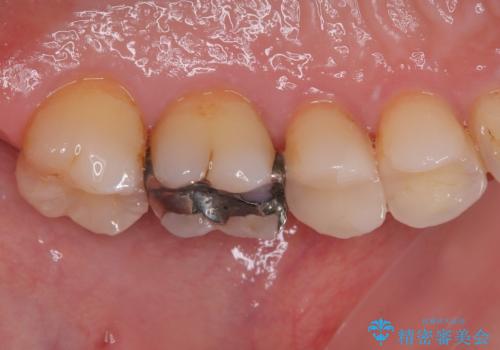

- 銀歯が取れたとのことで来院された患者様です。患者様の歯をあまり削りたくないというご希望に添い、セラミックインレーにて治療を行うこととなりました。

拡大鏡視野下で、保険のプラスチック、虫歯の除去を行い、セラミックインレーに適した形に整えました。

歯と歯茎の間に圧排糸と言われる糸を入れてシリコーン印象材にて精密な型どりをしました。

セラミックインレーの装着時には、唾液の侵入を防ぐために、ラバーダム防湿を行いました。